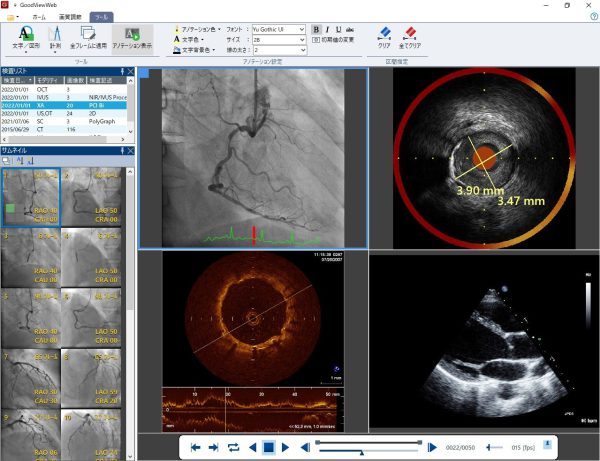

DICOMビューワとして医療画像活用の幅を広げてきたGoodViewに、より高度なエコー画像の計測機能が追加され、さらに使いやすくなる。追加された機能により心臓のボリュームの測定が簡単にできるようになり、収縮期と拡張期のボリュームの計測により循環器系の評価には重要で、専用機種やソフトではないと難しかった左室駆出率の算出も簡便に迅速に可能となる。これまで高位システムであるTomTec-Arenaでしか行えなかった高度な解析が一部GoodViewでも可能となり、より多くの医療現場での活用と迅速な診断につながることが期待される。本機能は2022年4月に認証を受け、同年夏ごろからバージョンアップが可能となる予定。

Cardiology総合管理ソリューション「Goodnet」は主に循環器分野で発生する検査画像の保存・配信はもちろん、複雑化するシステム連携やデータ管理、各種検査レポートの作成から画像解析まであらゆる場面で医療現場をサポート。

感染症対策などで激変する院内環境に対応すべく、Ver.7では施設内のどこでも専用端末と同じDICOM画像を同じ操作感で閲覧でき、くわえて検査レポートの承認ステータスも管理できるなどWebソリューションがより拡充。さらにはパニング撮影された下肢造影動画から下肢全長画像を自動で構築するツールや、AVI・JPG・PDFといった汎用ファイルの管理機能なども新たに標準搭載。